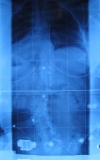

diese Woche hatte ich mein erstes Kontrollröntgen in meinem nun nicht mehr ganz so neuem Rahmouni Korsett! Habe mit Korsett eine Korrektur von lumbal 52° auf 30° und thorakal von 44° auf 23°. War ganz happy als ich meinen Rücken auf dem Röntgenbild gesehen habe.

- Röntgen ohne Korsett LW52° BW44°

- IMG_2866.JPG (19.59 KiB) 3261 mal betrachtet